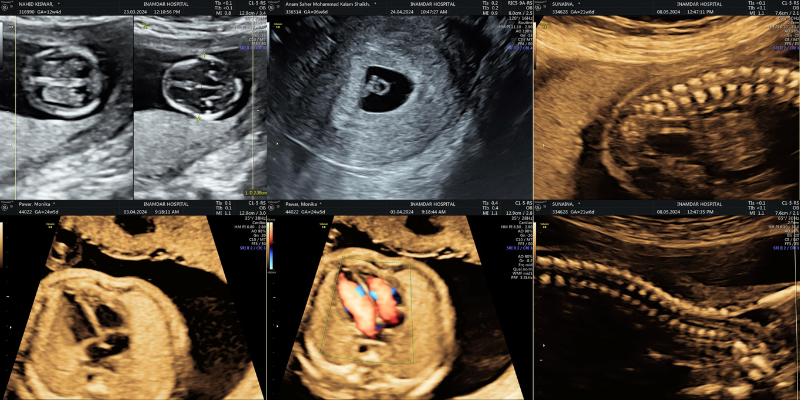

• 2D Ultrasound: Standard ultrasound, providing flat, black-and-white images of the body’s internal structures.

• 3D Ultrasound: Gives three-dimensional images, often used in pregnancy to see the baby’s facial features.

• 4D Ultrasound: Adds the dimension of motion to 3D images, capturing live video of the baby or organs.

• Doppler Ultrasound: Measures blood flow and helps diagnose issues like blockages or poor circulation.